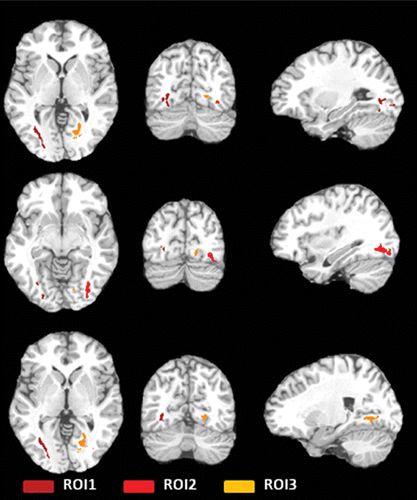

挪威的研究团队对39至68岁之间的前球员进行了脑部CT,发现有1/3的球员存在轻度至中度的脑萎缩现象。另一些研究人员则发现足球运动员的大脑存在脑白质(大脑内部神经纤维聚集的地方)微观结构的异常。

研究人员发现不少球员的大脑都存在一定问题